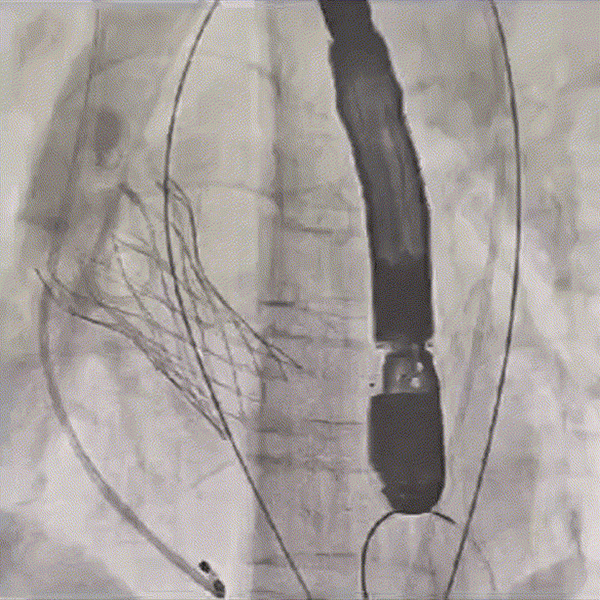

术后造影,瓣架形态良好

超声下血流动力学良好,无反流

术前V-max从4.1m/s下降至2m/s,PG 68mmHg下降至16.86mmHg。